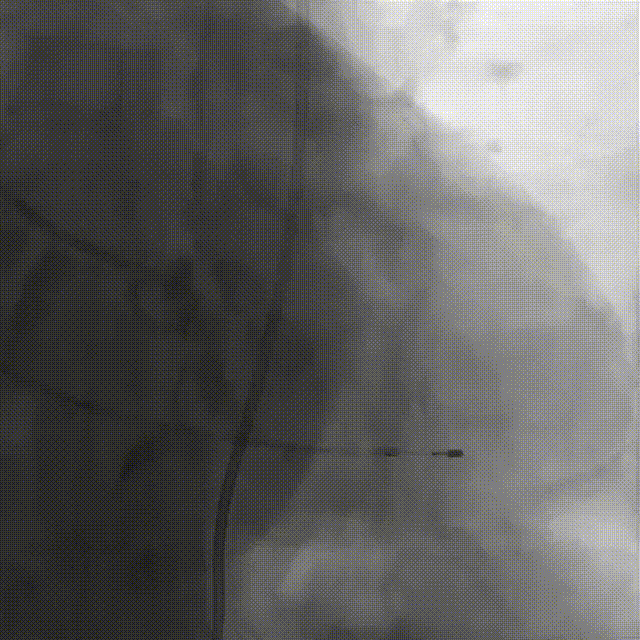

刘煜昊教授 阜外华中心血管病医院(点击查看专家详细简历) 首瓣选耐久,干瓣护航全生命周期管理 2025年ESC专家共识里指出:“推荐第一个瓣膜要选经证实具有长期耐用性的外科瓣膜与经导管瓣膜,以降低再次介入治疗的可能性 ,对于瓣环较小、根据预测有效瓣口面积(EOA)评估存在严重 PPM 风险的患者,可采用主动脉根部扩大术联合 SAVR,或植入环上瓣,对于小瓣环患者自展瓣拥有比较好的血流动力学优势”。 每一次术前评估,都是我们与患者携手面对未知的起点。我们始终以患者全生命周期获益为核心,在瓣膜选择与术式规划中,不只着眼于当下解剖适配,综合评估解剖条件、预期寿命与生活质量。从年轻患者到高龄人群,瓣膜耐久性与血流动力学稳定性始终是决策核心! 陈同峰教授 阜外华中心血管病医院(点击查看专家详细简历) 医学的进步正不断拓宽生命的边界,每一次术前评估都是对生命尊严的深度凝视,技术与人文的交融,让风险不再仅是数字的堆叠,而是成为医者与患者共同面对未知的勇气见证。术中瓣膜释放结束,到了导管测压的时候,我惊喜:瓣膜不错啊,压差为0,这不仅仅得益于瓣膜形态的设计,更是环上瓣及瓣叶材质优质的体现,感受到了 Prostyle A瓣膜在血流动力学上的卓越表现,其采用的抗钙化处理技术有效延长了瓣膜的耐久性,为患者长期生存提供了更可靠的保障。 患者病史 主诉:心慌半月; 门急诊诊断:心悸,冠状动脉粥样硬化性心脏病,心脏瓣膜病,主动脉瓣狭窄,高血压,甲状腺术后; 现病史:半月前无明显诱因出现心慌,呈间断性,伴心悸、出汗,伴头晕,无咳嗽、咳痰,无恶心、呕吐,无双下肢水肿,无放射痛及意识障碍,休息约几分钟后可自行缓解,症状反复发作,遂来我院就诊。 术前超声提示:室间隔增厚;主动脉瓣退行性变并重度狭窄;升主动脉明显增宽;室间隔增厚。 术前CT 三叶瓣,轻度钙化集中在无窦和左窦瓣叶边缘,主动脉根部直径19.3mm,LVOT直径17.7mm,LVOT向下收窄; 窦部正常,VTC空间足够,冠脉风险低; 左室腔小,收缩末径20-25mm,“自杀左室”,循环崩溃风险高;主动脉瓣环水平夹角71.1°,横位心,过弓和跨瓣存在一定困难,备snare。 外周双侧入路内径可,双侧入路能够支持20F大鞘通过,右股低分叉。 手术策略 推荐右侧股动脉为主入路,左侧为辅助入路,右股分叉上方1cm穿刺;推荐选择AV23瓣膜,18mm球囊预扩,左右重叠位:LAO 7° CAU 35°;左冠切线位:LAO 27° CRA 16°;右窦居中位:LAO 18° CAU 9°;备Snare,建议ECMO/CPB湿备,术前术中积极补液,警惕循环崩溃风险。 手术过程 在右股动脉穿刺建立通路后,顺利送入大鞘,经食道超声及血管造影确认路径稳定。18mm球囊预扩过程中,患者血压一度下降,迅速完成扩张并立即植入AV23 ProStyle A®瓣膜。瓣膜精准释放于目标位置,超声显示无明显反流及瓣周漏,血流动力学即刻改善。 主动脉根部造影 18mm球囊预扩少量反流 输送系统柔顺跨瓣 精准定位 平稳释放 80%工作位观索位置合适 释放后导管测压,压差由术前53mmHg降为0mmHg 最终造影瓣膜位置形态良好,冠脉灌注良好,无明显瓣周漏 ProStyle A®预装干瓣——助力临床最优化解决方案: 轻松过弓,精准可控:该病例为横位心,在未使用snare的情况下,过弓和跨瓣柔顺,较细的尺寸+柔顺的输送系统通过性能得到了很好的验证; 平衡的收腰设计:该病例瓣环较小且左室腔小,AV23瓣膜的平衡收腰设计既确保了锚定安全性,又保证了EOA,有效降低了循环崩溃风险,而术后0mmHg的压差的表现更加证明了优秀的血流动力学,提高了瓣膜的耐久性; 预装干瓣 便捷顺安:金仕生物专利抗钙化技术运用纳米技术去除组织内的细胞碎片和磷脂,封闭游离醛基,从根本上阻断了瓣膜钙化的多项因素,显著提升了瓣膜的耐久性;同时,相比较传统戊二醛保存方式,干式存储最大限度的保留心包的亲水亲油平衡,还原组织天然曲柔性,进一步保障了瓣叶开合,保证长期耐久性。 专家简介 王小虎 阜外华中心血管病医院(点击查看专家详细简历) 陈冲 阜外华中心血管病医院(点击查看专家详细简历) 赵一品 阜外华中心血管病医院(点击查看专家详细简历)